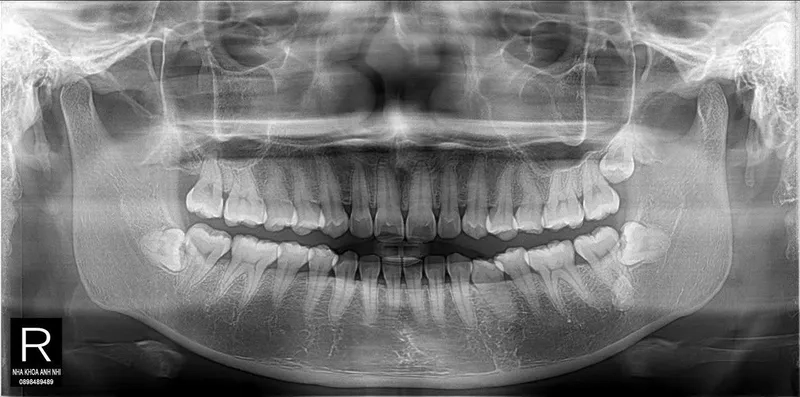

Chính vì là kẻ đến sau cùng, răng khôn thường không tìm được vị trí thuận lợi để mọc thẳng. Chúng phải tìm cách chen chúc, dẫn đến các tình trạng phổ biến như mọc lệch, mọc ngầm dưới nướu hoặc đâm ngang vào chiếc răng số 7 bên cạnh.

Khi răng khôn mọc lệch hoặc đâm ngang, nó sẽ trực tiếp húc vào chân răng số 7. Lực đẩy này diễn ra âm thầm nhưng mạnh mẽ, làm tiêu chân răng, gây sâu răng số 7 và có thể khiến chiếc răng này bị lung lay hoặc mất vĩnh viễn.

Xô lệch toàn bộ hệ thống hàm răng

Nguy cơ hình thành u nang xương hàm

Trong một số trường hợp răng khôn mọc ngầm hoàn toàn trong xương, các mô bao quanh răng có thể phát triển thành u nang.

Nếu không được phát hiện qua phim chụp X-quang, u nang này sẽ âm thầm phá hủy xương hàm, làm tổn thương các dây thần kinh và các răng xung quanh, gây ra những tổn thương nặng nề khó phục hồi.